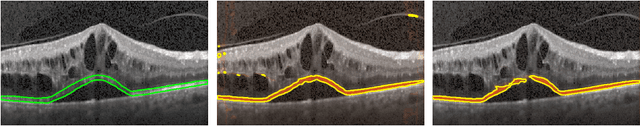

Abstract:Segmenting anatomical structures such as the photoreceptor layer in retinal optical coherence tomography (OCT) scans is challenging in pathological scenarios. Supervised deep learning models trained with standard loss functions are usually able to characterize only the most common disease appeareance from a training set, resulting in suboptimal performance and poor generalization when dealing with unseen lesions. In this paper we propose to overcome this limitation by means of an augmented target loss function framework. We introduce a novel amplified-target loss that explicitly penalizes errors within the central area of the input images, based on the observation that most of the challenging disease appeareance is usually located in this area. We experimentally validated our approach using a data set with OCT scans of patients with macular diseases. We observe increased performance compared to the models that use only the standard losses. Our proposed loss function strongly supports the segmentation model to better distinguish photoreceptors in highly pathological scenarios.